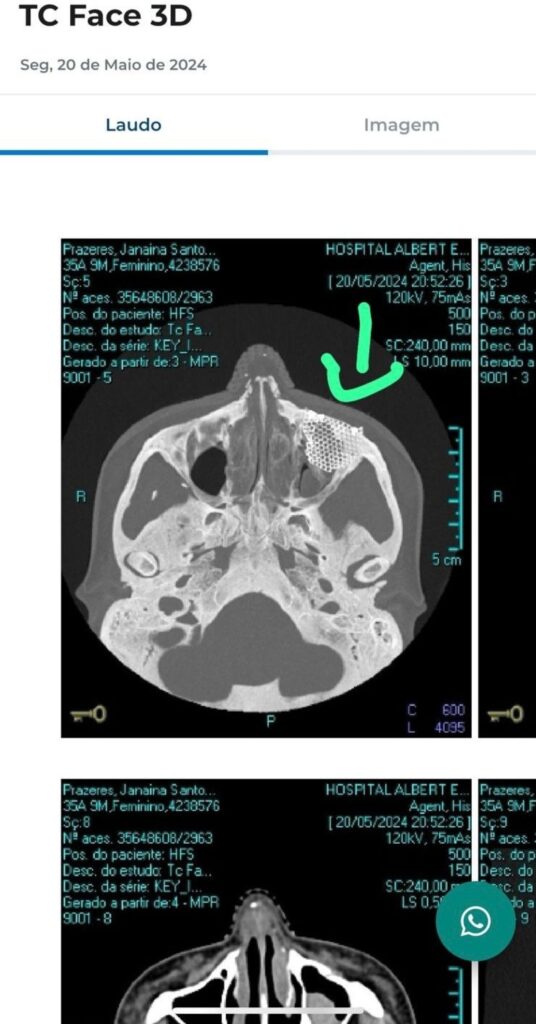

Após o ataque, Janaina teve que passar por uma cirurgia complexa que incluiu a colocação de uma placa de titânio no rosto. Ela comentou sobre a experiência e como tem lidado com as consequências físicas e psicológicas do ocorrido. “A placa é imperceptível a olho nu, só dá para saber se tocar no meu rosto, porque dá para sentir os parafusos”, explicou a influenciadora.